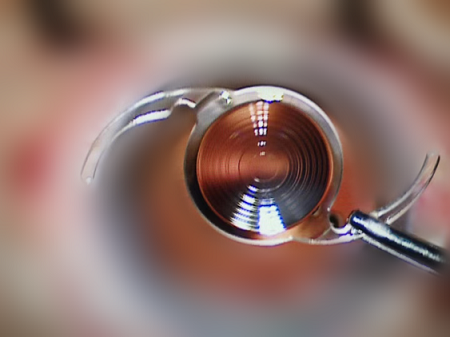

新一代Synergy?躍無級?人工晶體在?,敻髟簭V泛應(yīng)用

為滿足患者日益提升的視覺需求,希瑪眼科引進TECNIS Synergy?躍無級?人工晶狀體,為白內(nèi)障患者提供更好的視覺體驗和更高的生活質(zhì)量.

?,斞劭圃诎變?nèi)障手術(shù)領(lǐng)域率先引入創(chuàng)新產(chǎn)品與技術(shù),采用高端診療科技,為患者保駕護航.TECNIS Synergy?躍無級?人工晶狀體植入術(shù)的臨床應(yīng)用,將進一步提升屈光白內(nèi)障患者術(shù)后視覺質(zhì)量,為國內(nèi)白內(nèi)障與老花眼的患者,提供從遠(yuǎn)到近全程距離的高質(zhì)量完整視力.

相較于傳統(tǒng)晶體,TECNIS Synergy?躍無級?人工晶狀體融合了EDOF連續(xù)視程和多焦的技術(shù),讓患者在焦點之間任何一個點上,都能看得更清、看得完整,改善了三焦點人工晶狀體不同焦點之間視力突然驟降的問題,在更近的距離上擁有更好的近視力.

簡單來說,TECNIS Synergy?躍無級?人工晶狀體能夠在模擬自然眼的同時,增強圖像對比敏感度,提高患者暗光下的視覺質(zhì)量,患者植入后無需伸長手臂或迎合人工晶狀體的焦點距離,更適合中國患者近距離的用眼需求.

TECNIS Synergy?躍無級?人工晶狀體人工晶狀體,可以在連續(xù)范圍內(nèi)提供清楚聚焦圖像,從而看清楚軸向上不間斷距離上的物體,為廣大白內(nèi)障與老花眼患者,提供從33cm到遠(yuǎn)距離的良好連續(xù)視力.

除此之外,TECNIS Synergy?躍無級?人工晶狀體

可以清楚捕獲從遠(yuǎn)到近任意距離,即使在暗光條件下,也能提供良好的暗視力,獲取完整、連續(xù)、動態(tài)的良好視覺體驗,讓患者能完整看到每一個精彩的瞬間.